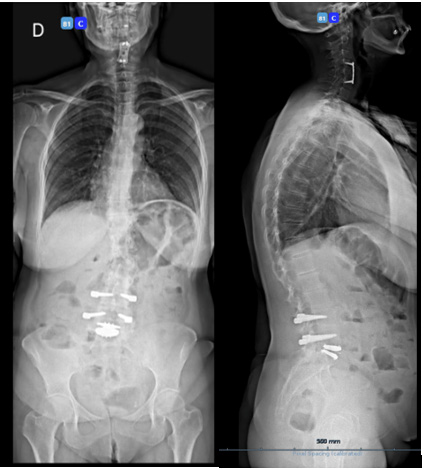

We present the case of a 40-year-old woman who presented with low back pain resistant to analgesics and rehabilitation. She was compensated and had excellent flexion and extension of her spine. The patient had a normal neurologic examination of the lower extremities. Radiographic evaluation revealed good sagittal and coronal balance, despite the co-existing mild thoracolumbar scoliosis. MRI showed Degenerative Disc Disease (DDD) at L4-L5 and L5-S1 (Figure 1A-B). She underwent a lumbar Total Disc Replacement (TDR) at L5–S1with the Charité III prosthesis and Posterior Transpedicular Dynamic Stabilization (PDS) with the Dynesys system at L4-L5 in 2001. Post-operatively, there was significant clinical improvement and the patient went back to work. In 2014, the patient complained of unremitting axial low back pain, aggravated by walking and sitting with increasing difficulty standing and looking straight ahead when walking. Concurrently, polyarthralgia and throcanteritis were also present. This motivated evaluation by Rheumatology for autoimmune disease screening which was negative. Despite being subjected to a new rehabilitation protocol, there was no clinical improvement. X rays showed a degenerative scoliosis with sagittal and coronal imbalance (Figure 2A-B) with multiple discopathies and syndesmophytes through the lumbar and thoracic spine. TDR and PDS were stable and in good position. MRI showed Dark Disc Disease at D11-D12 and from L1-L2 to L4- L5 (Figure 3A-B). The patient underwent a Transforaminal Lumbar Interbody Fusion (TLIF) at L3-L4, PDS removal and T4-L5 posterior fusion in November 2018. At the moment, the patient maintains reported significant improvement in her back pain and reduction in the requirement of analgesic medicines. Physical exam shows good spinopelvic mobility (Figure 4). Radiographs reveal good coronal and sagittal balance and satisfactory position of the total disc replacement and good fusion of the thoracic and lumbar spine proximally (Figure 5A-B) (Figure 6A-B).